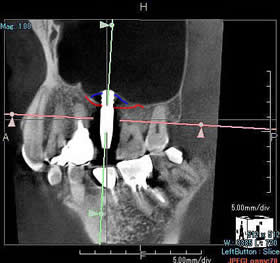

volumeをXYZ方向にそれぞれ512分割しておりこのときのスライスピッチは標準モード撮影で147㎛、高解像度モード撮影(ハイレゾ)で101㎛です。 3D画像はリアルタイムで自由に動かすことができるので骨の形態や奥行きを容易に把握できます。 さらにウィンドウレベルを操作することでさまざまな画像を簡単に得ることができます。 またインプラント治療においては下顎管やオトガイ孔、上顎洞下壁までの距離を正確に測定できるので術中も安全に治療をおこなうことができます。 |

矢状断での術前シュミレーション

(約3㎜程度のソケットリフトが必要)

直径2㎜のガイドドリルで深さ5㎜でドリリング

した後、方向チェッカーを挿入し距離を確認。

(洞底側皮質骨に到達)